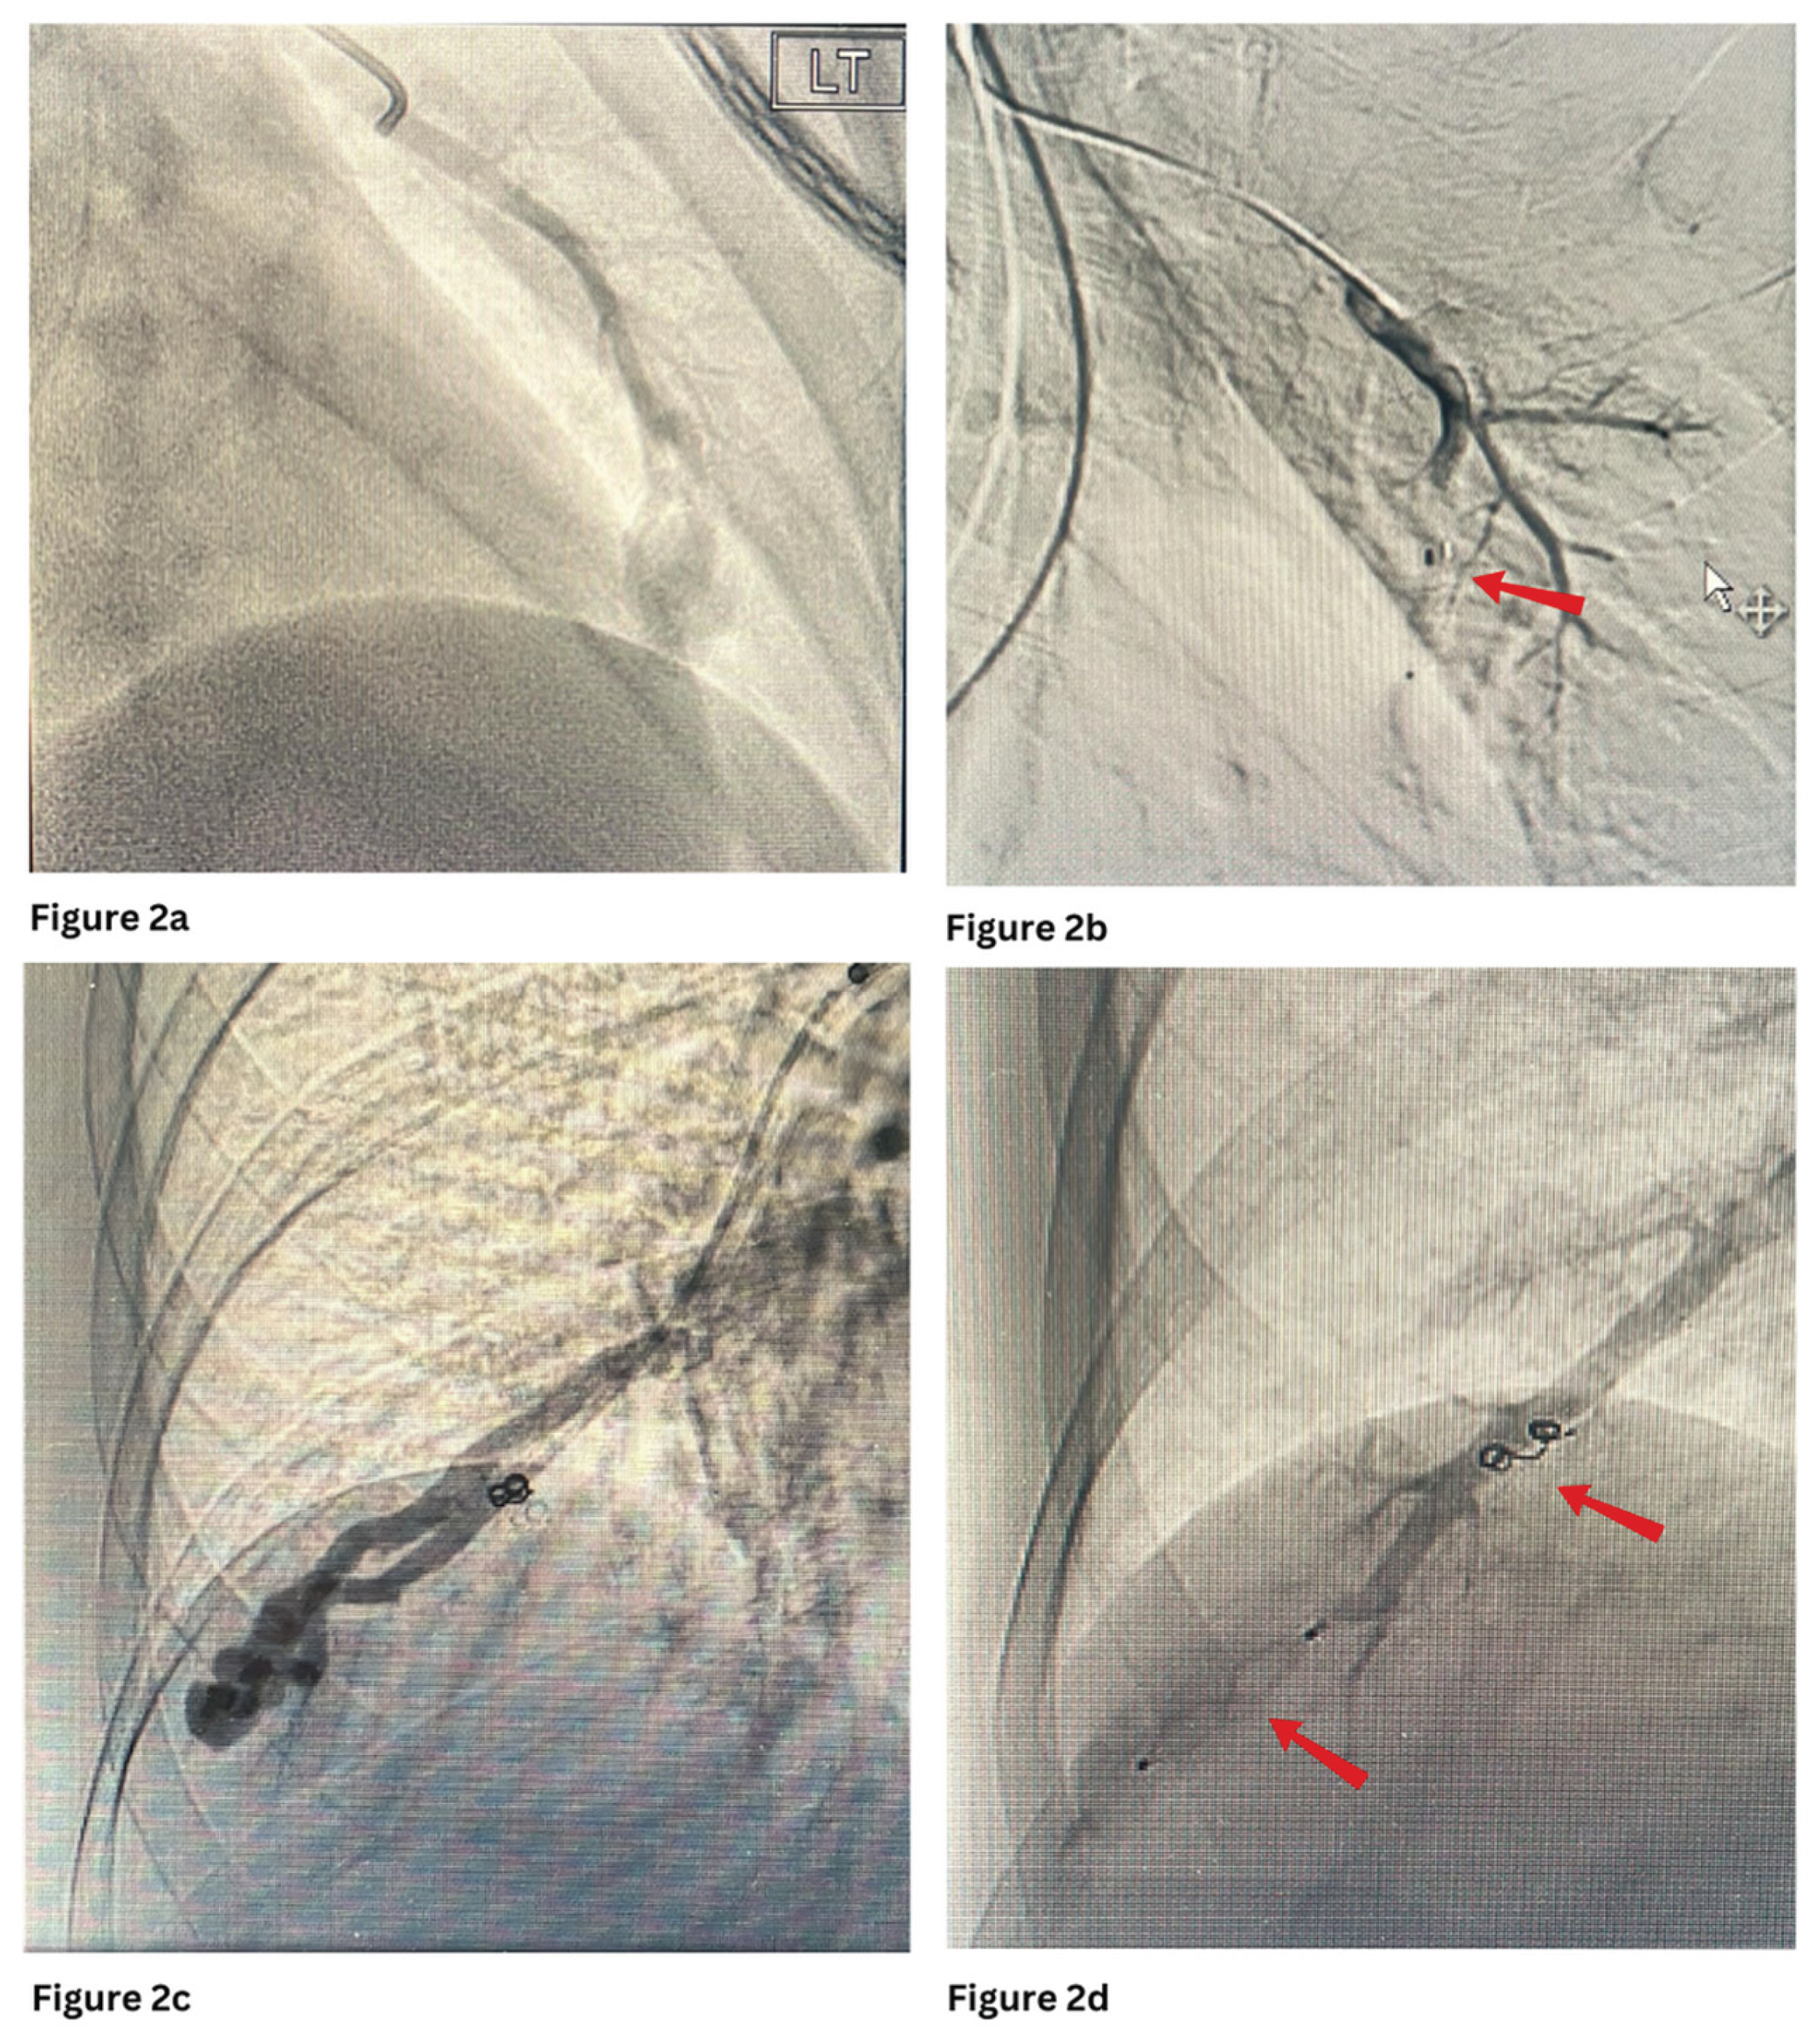

Figure 1 and Figure 3 show PAVMs embolised using detachable coils and/or AVP in simple and complex PAVMs, respectively.

Figure 1. a and b show pre and post embolization of the PAVM with multiple coils at the right lower lobe. c and d show pre and post embolization of the complex PAVM with 2 AVP plugs at the left lower lobe.